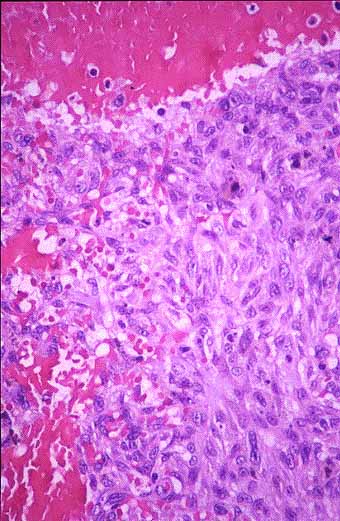

Fig 4

Fig 4.- La lesión muestra polimorfismo celular con presencia de células gigantes y depósitos de hemosiderina. (H&E, 200x).